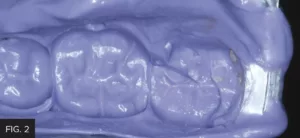

In any clinical setting, available chair time may be limited and may not allow for obtaining an impression of the fractured tooth along with the opposing dentition and fabricating a temporary matrix from an ideal wax-up. Therefore, the clinician may build up the tooth with old or expired composite or wax and then take an impression of the tooth. One challenge with this method, however, is that the composite or wax buildup may dislodge from the tooth in the process of taking the impression of the tooth. In order to avoid this another technique was utilized. An impression of the non-intact tooth was taken using Template Ultra Quick Matrix Material (Clinician’s Choice) in a Quad-Tray Xtreme (Clinician’s Choice) dual-arch impression tray. (FIG 2)